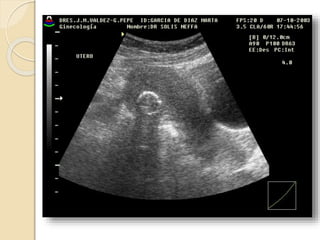

Quistes Funcionales

Quistes foliculares:

Resultan de una falla en la involución.

El folículo se distiende y mide mas de

30mm de diámetro. No dan síntoma a

menos que adquieran mucho tamaño y

sufran ruptura, torsión o hemorragia

Quistes Funcionales Quistesfoliculares: Resultan de una falla en la involución. El folículo se distiende y mide mas de 30mm de diámetro. No dan síntoma a menos que adquieran mucho tamaño y sufran ruptura, torsión o hemorragia